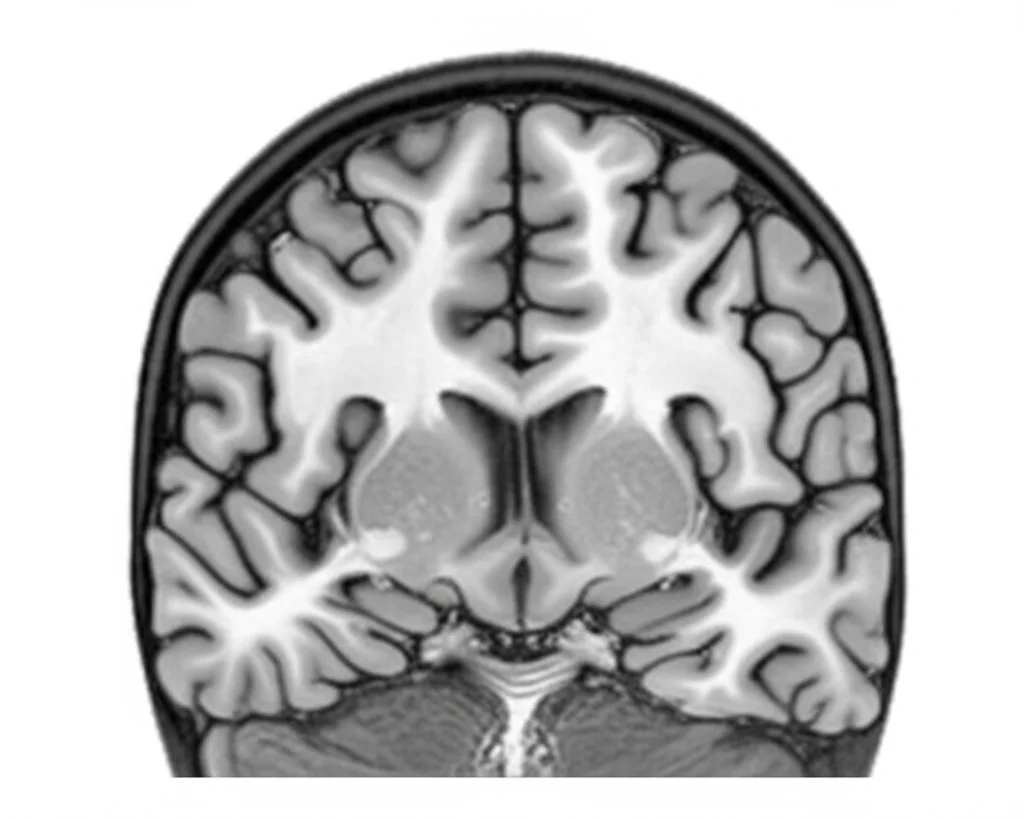

Abbiamo anche scoperto che i geni prioritari legati all’AOW sono particolarmente attivi nel cervello durante specifiche fasi dello sviluppo prenatale, tra la 19esima e la 24esima settimana post-concezionale. E le analisi sui tipi di cellule hanno puntato i riflettori su aree cerebrali cruciali per il controllo motorio come i gangli della base, la corteccia e il cervelletto.

- Una correlazione genetica positiva con la girificazione cerebrale (il grado di “pieghe” della corteccia cerebrale, un segno di complessità) sia nei neonati che negli adulti, e con il livello di istruzione e le prestazioni cognitive. Qui, una predisposizione genetica a camminare più tardi sembra andare di pari passo con una maggiore girificazione e migliori risultati cognitivi ed educativi. Forse un periodo di neurogenesi sottocorticale più protratto nel periodo prenatale, che porta a un inizio più tardivo della deambulazione, permette alle regioni corticali coinvolte in comportamenti motori più complessi di specializzarsi più a lungo.

Ma c’è di più: abbiamo testato questo PGS su dati di imaging cerebrale neonatale. E indovinate un po’? Un PGS più alto (che predispone a un’età dei primi passi più tardiva) era associato a un maggiore volume di alcune strutture cerebrali neonatali coinvolte nel controllo motorio, come i gangli della base, il talamo posteriore destro, i talami anteriori bilaterali, il cervelletto e i peduncoli cerebellari, il ponte e il midollo. Inoltre, un PGS più alto era associato a una maggiore girificazione cerebrale nei neonati. E, come se non bastasse, in un follow-up a 18 mesi, un PGS più alto per l’AOW era associato a punteggi motori grossolani leggermente inferiori nelle scale Bayley, suggerendo abilità motorie forse un po’ più tardive.